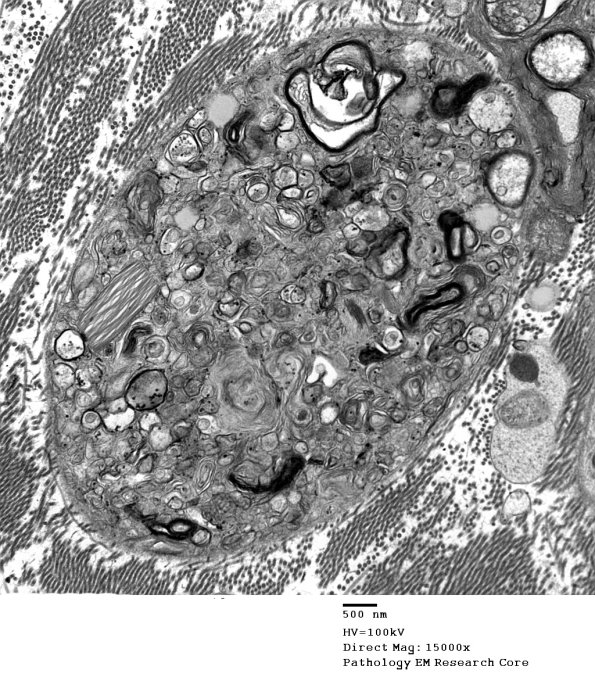

2E3,4 A complex admixture of all the myelin, axon and Schwann cell cytoplasm.